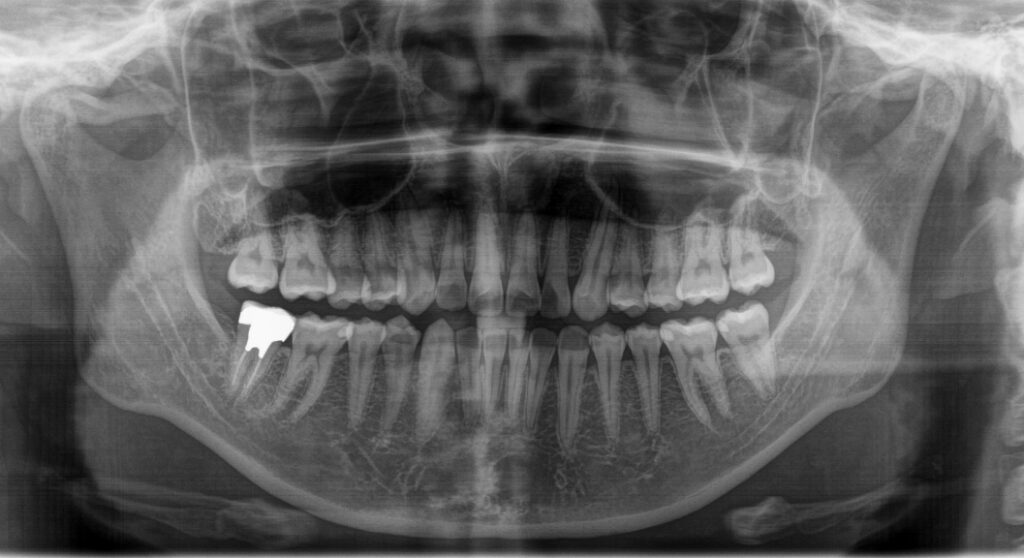

3.レントゲン撮影(2種類)

お口全体のレントゲンと一部を詳しく写すレントゲンの2種類を撮影いたします。

(必要に応じて、追加撮影させていただくこともあります。)

こちらは、見た目ではわからない虫歯や、歯の根っこ、骨の状態などを確認するためには必要な検査になります。